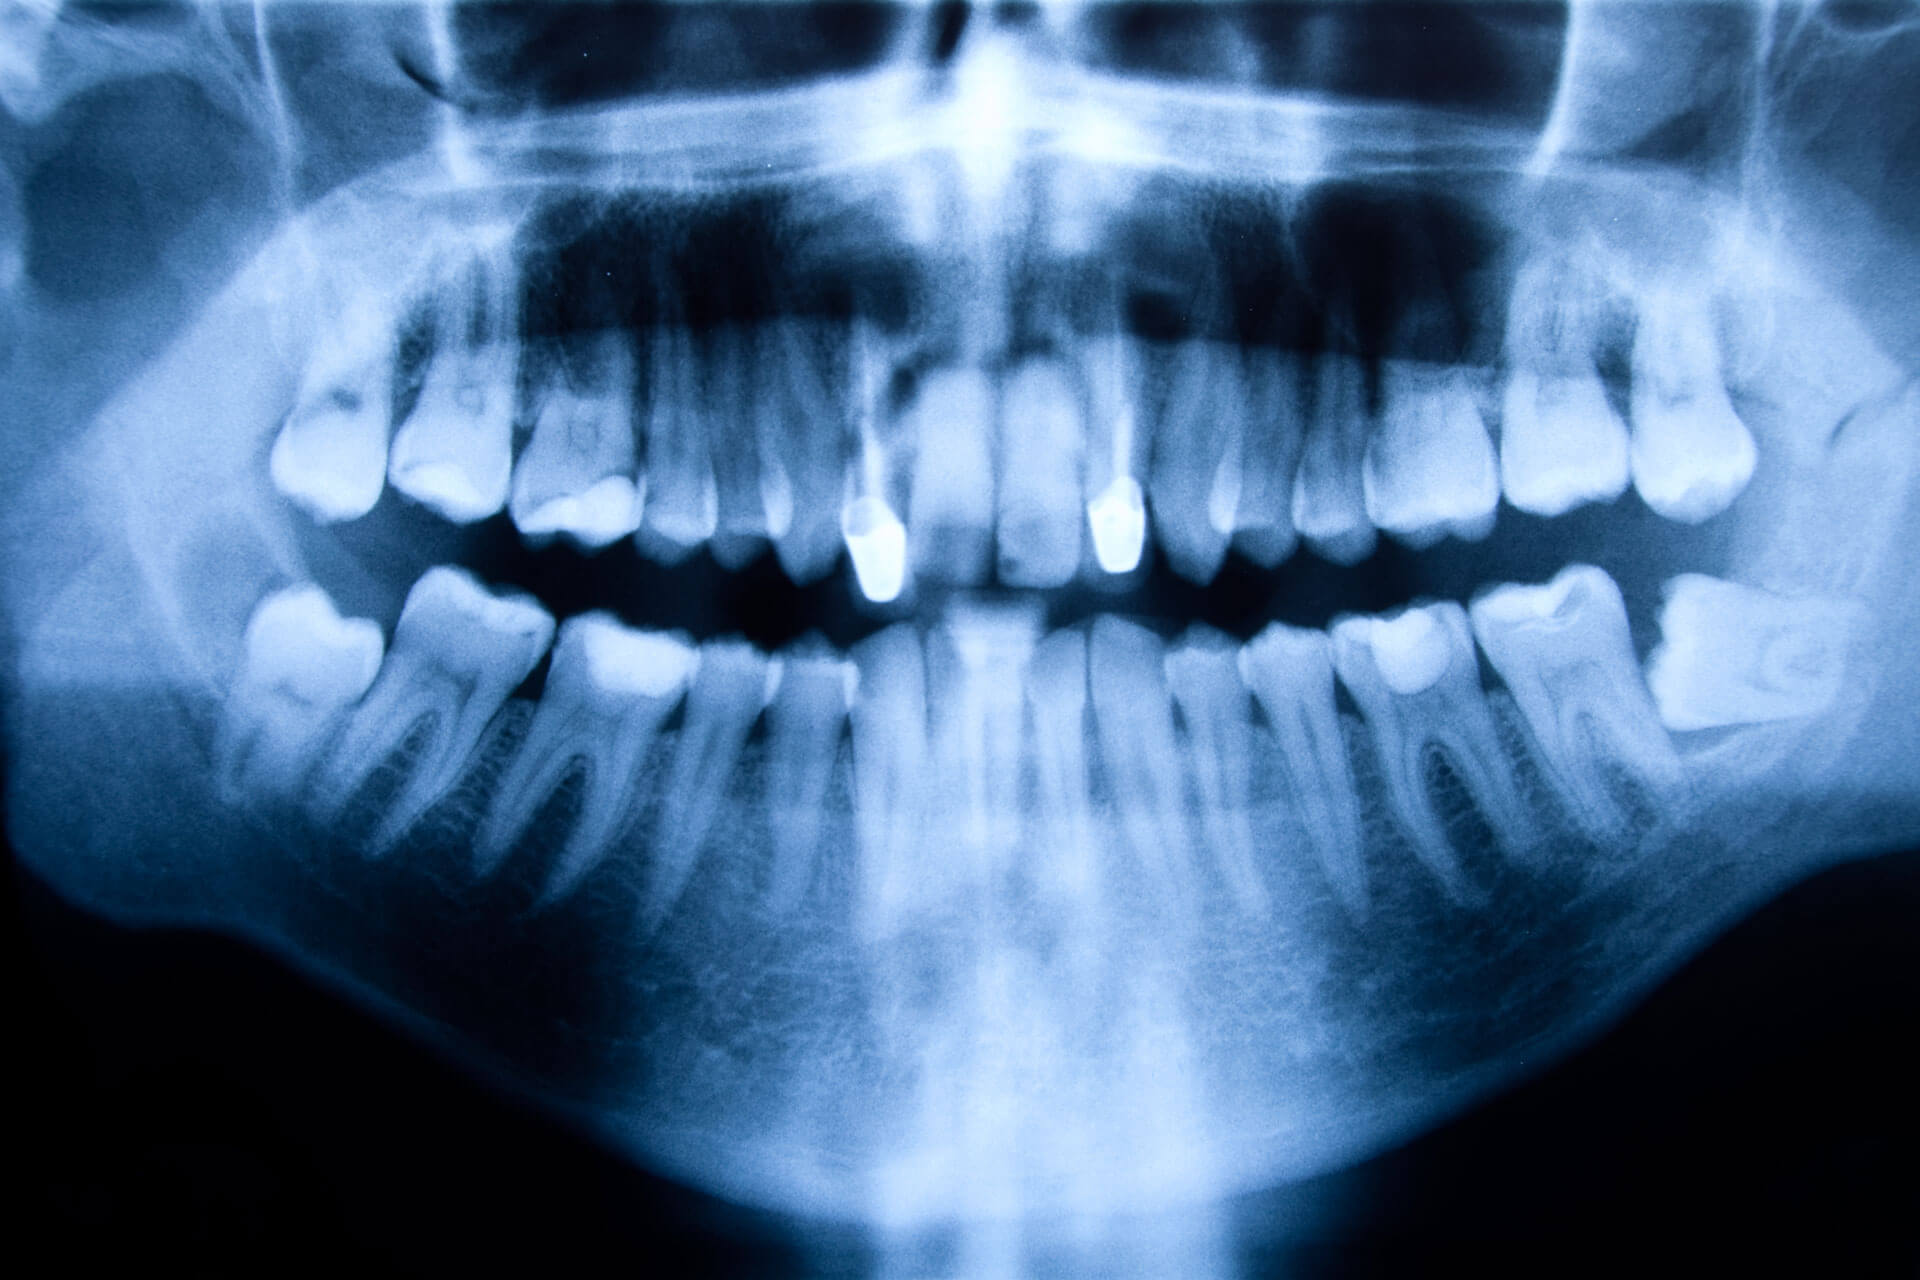

Suspectant un kyste, le dentiste prendra des radiographies de la bouche afin de déterminer l’emplacement exact, la taille, l’état de la dent qui en est à l’origine et les structures voisines impliquées. Parfois, il peut aussi demander d’autres examens complémentaires, comme la ponction ou l’aspiration du kyste pour étudier la nature de ses cellules au microscope.

Ensuite, l’évolution de la condition est contrôlée par des rayons X. Puis, si la lésion persiste, une petite intervention chirurgicale est nécessaire pour retirer définitivement le kyste.

- Résorption des racines des dents près du kyste (cela se voit avec les radiographies dentaires).